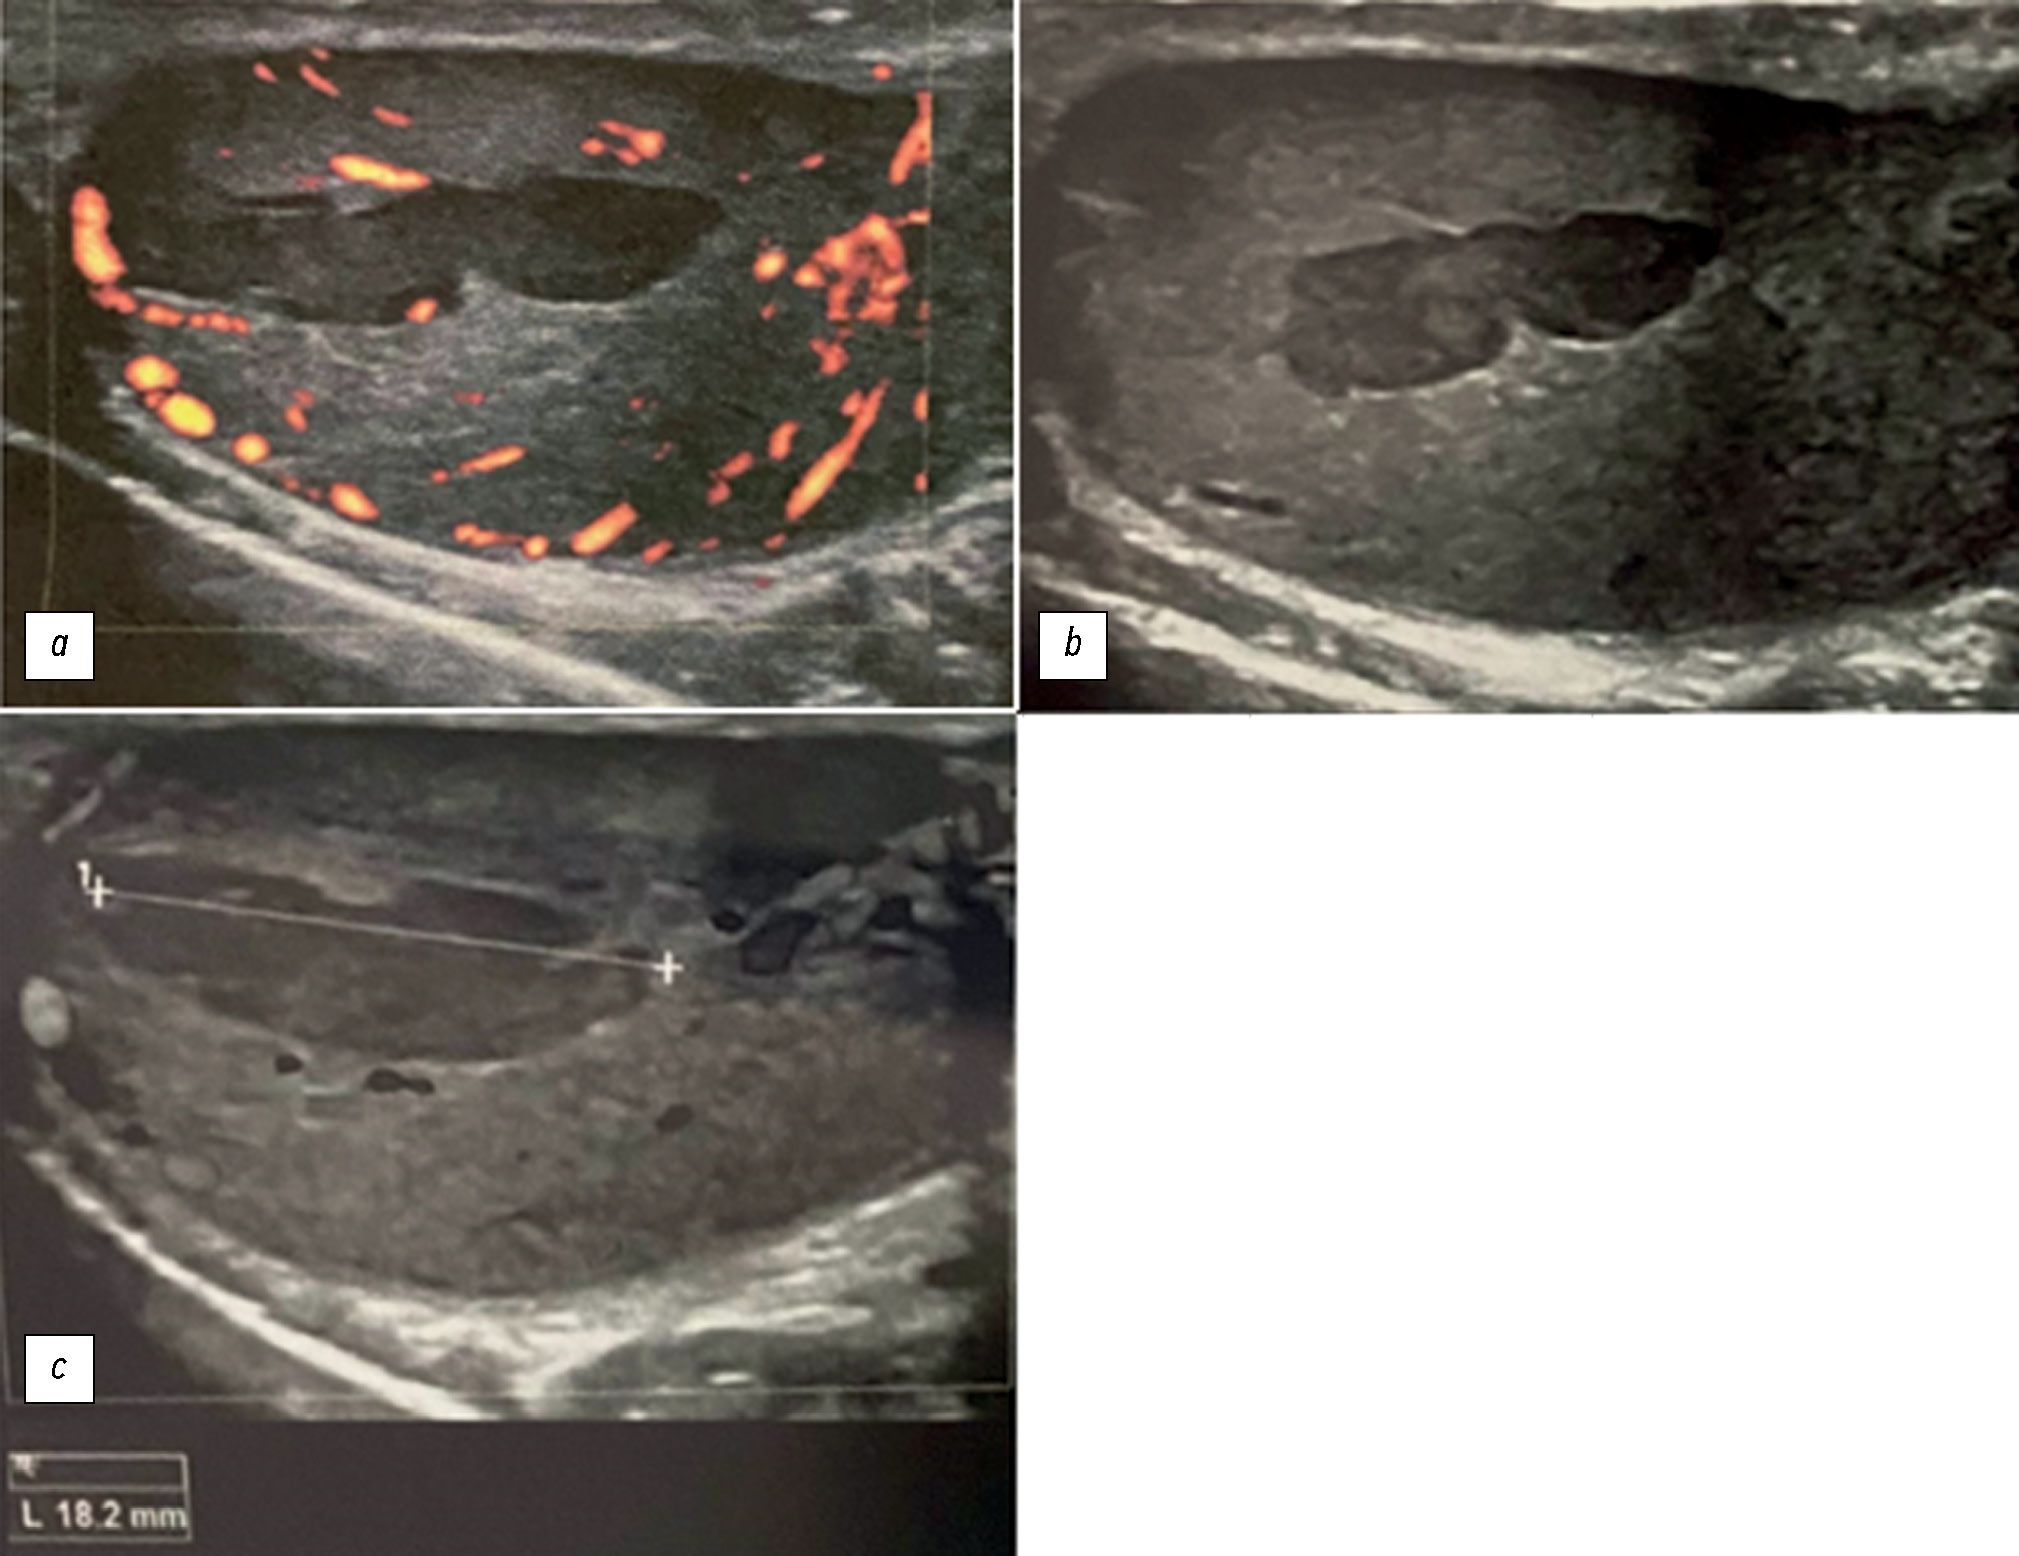

Было выполнено ультразвуковое исследование (УЗИ) мошонки. По его результатам выявлено нормальное расположение и структура правого яичка (диаметр 40 мм, общий объём 22 мл) при наличии отёчности, повышении температуры и уменьшении размеров левого яичка (диаметр 38 мм, общий объём 18 мл) [2, 3]. Кроме того, установлены неравномерная эхогенность и отёчность придатка левого яичка. По результатам УЗИ наличие гипоэхогенной области вытянутой овальной формы с неровными краями (длиной около 18,2 мм) указывало на неоднородность структуры левого яичка (рис. 1).

Рис. 1. При ультразвуковом исследовании отмечена неоднородность эхоструктуры и отёчность левого яичка, в тканях которого наблюдалась повышенная васкуляризация (a) за исключением протяжённой области овальной формы длиной около 18,2 мм (c). Данная область характеризовалась отсутствием допплеровского сигнала (b), что дало основания подозревать инфаркт. Ультразвуковое исследование на ранней стадии заболевания не позволяет выявить каких-либо нарушений. По мере течения заболевания (как в данном случае) область ишемии становится гипоэхогенной: на изображениях яичка в поперечной и продольной проекции визуализируется гипоэхогенный очаг поражения клиновидной овальной формы, пересекающий яичко поперёк, с вершиной в области средостения яичка.